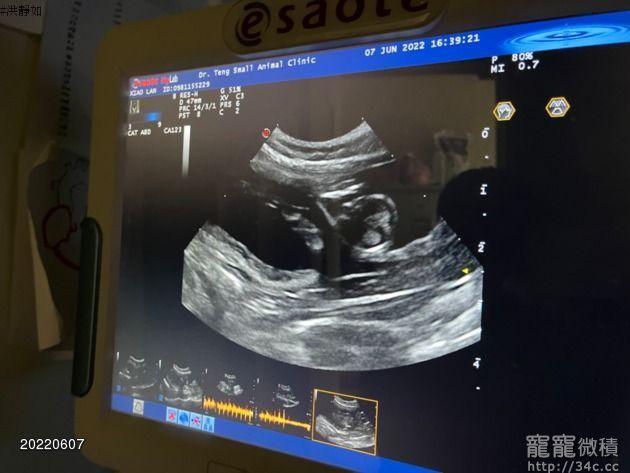

重點色小布偶母貓一次懷孕四隻會不會太多? 禁止回覆

如果太多隻會不會難產?

目前母貓3.2公斤